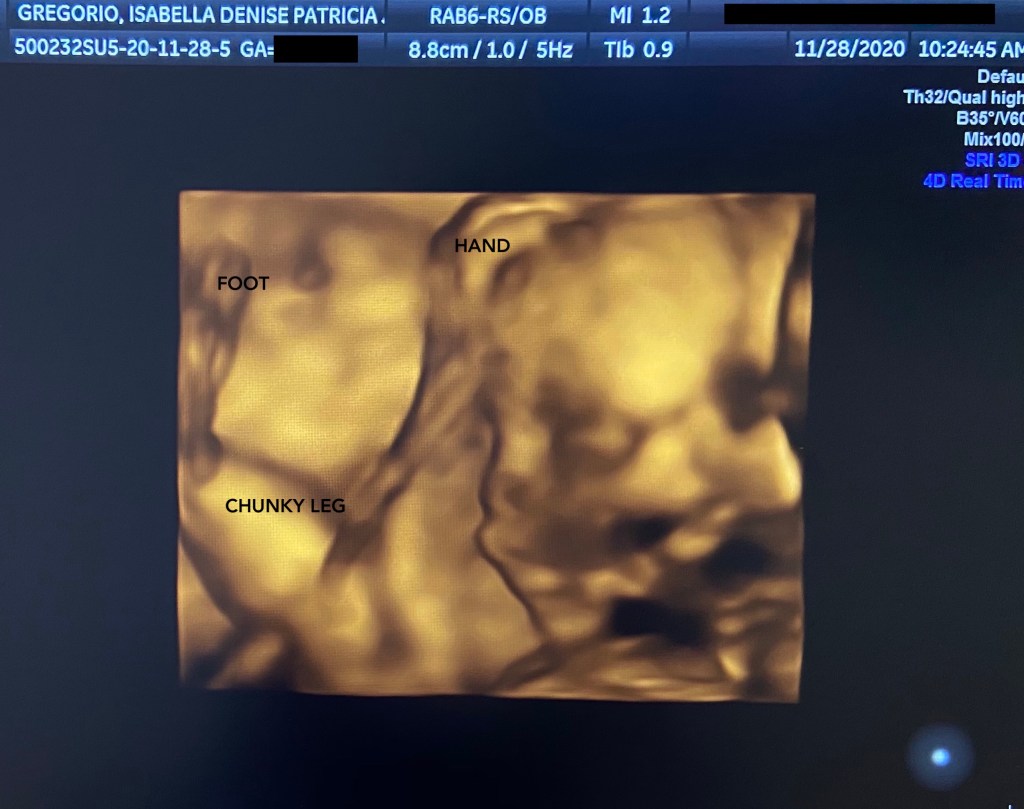

I am now in my 6th month of pregnancy. I decided to keep it private for as long as I could—not because I wasn’t keen on sharing the wonderful news—but because for the first time in my life, I felt I had something awfully precious to protect. Life in the digital age demands copious amounts of consent and energy; it’s a vicious cycle of snapping, sharing and scrolling. While I’ve always been an open book, I wanted to bask in the moment as privately as I could, and for as long as I possibly could.

I wanted to keep this beautiful miracle further away from public view and tucked safely inside my growing belly.